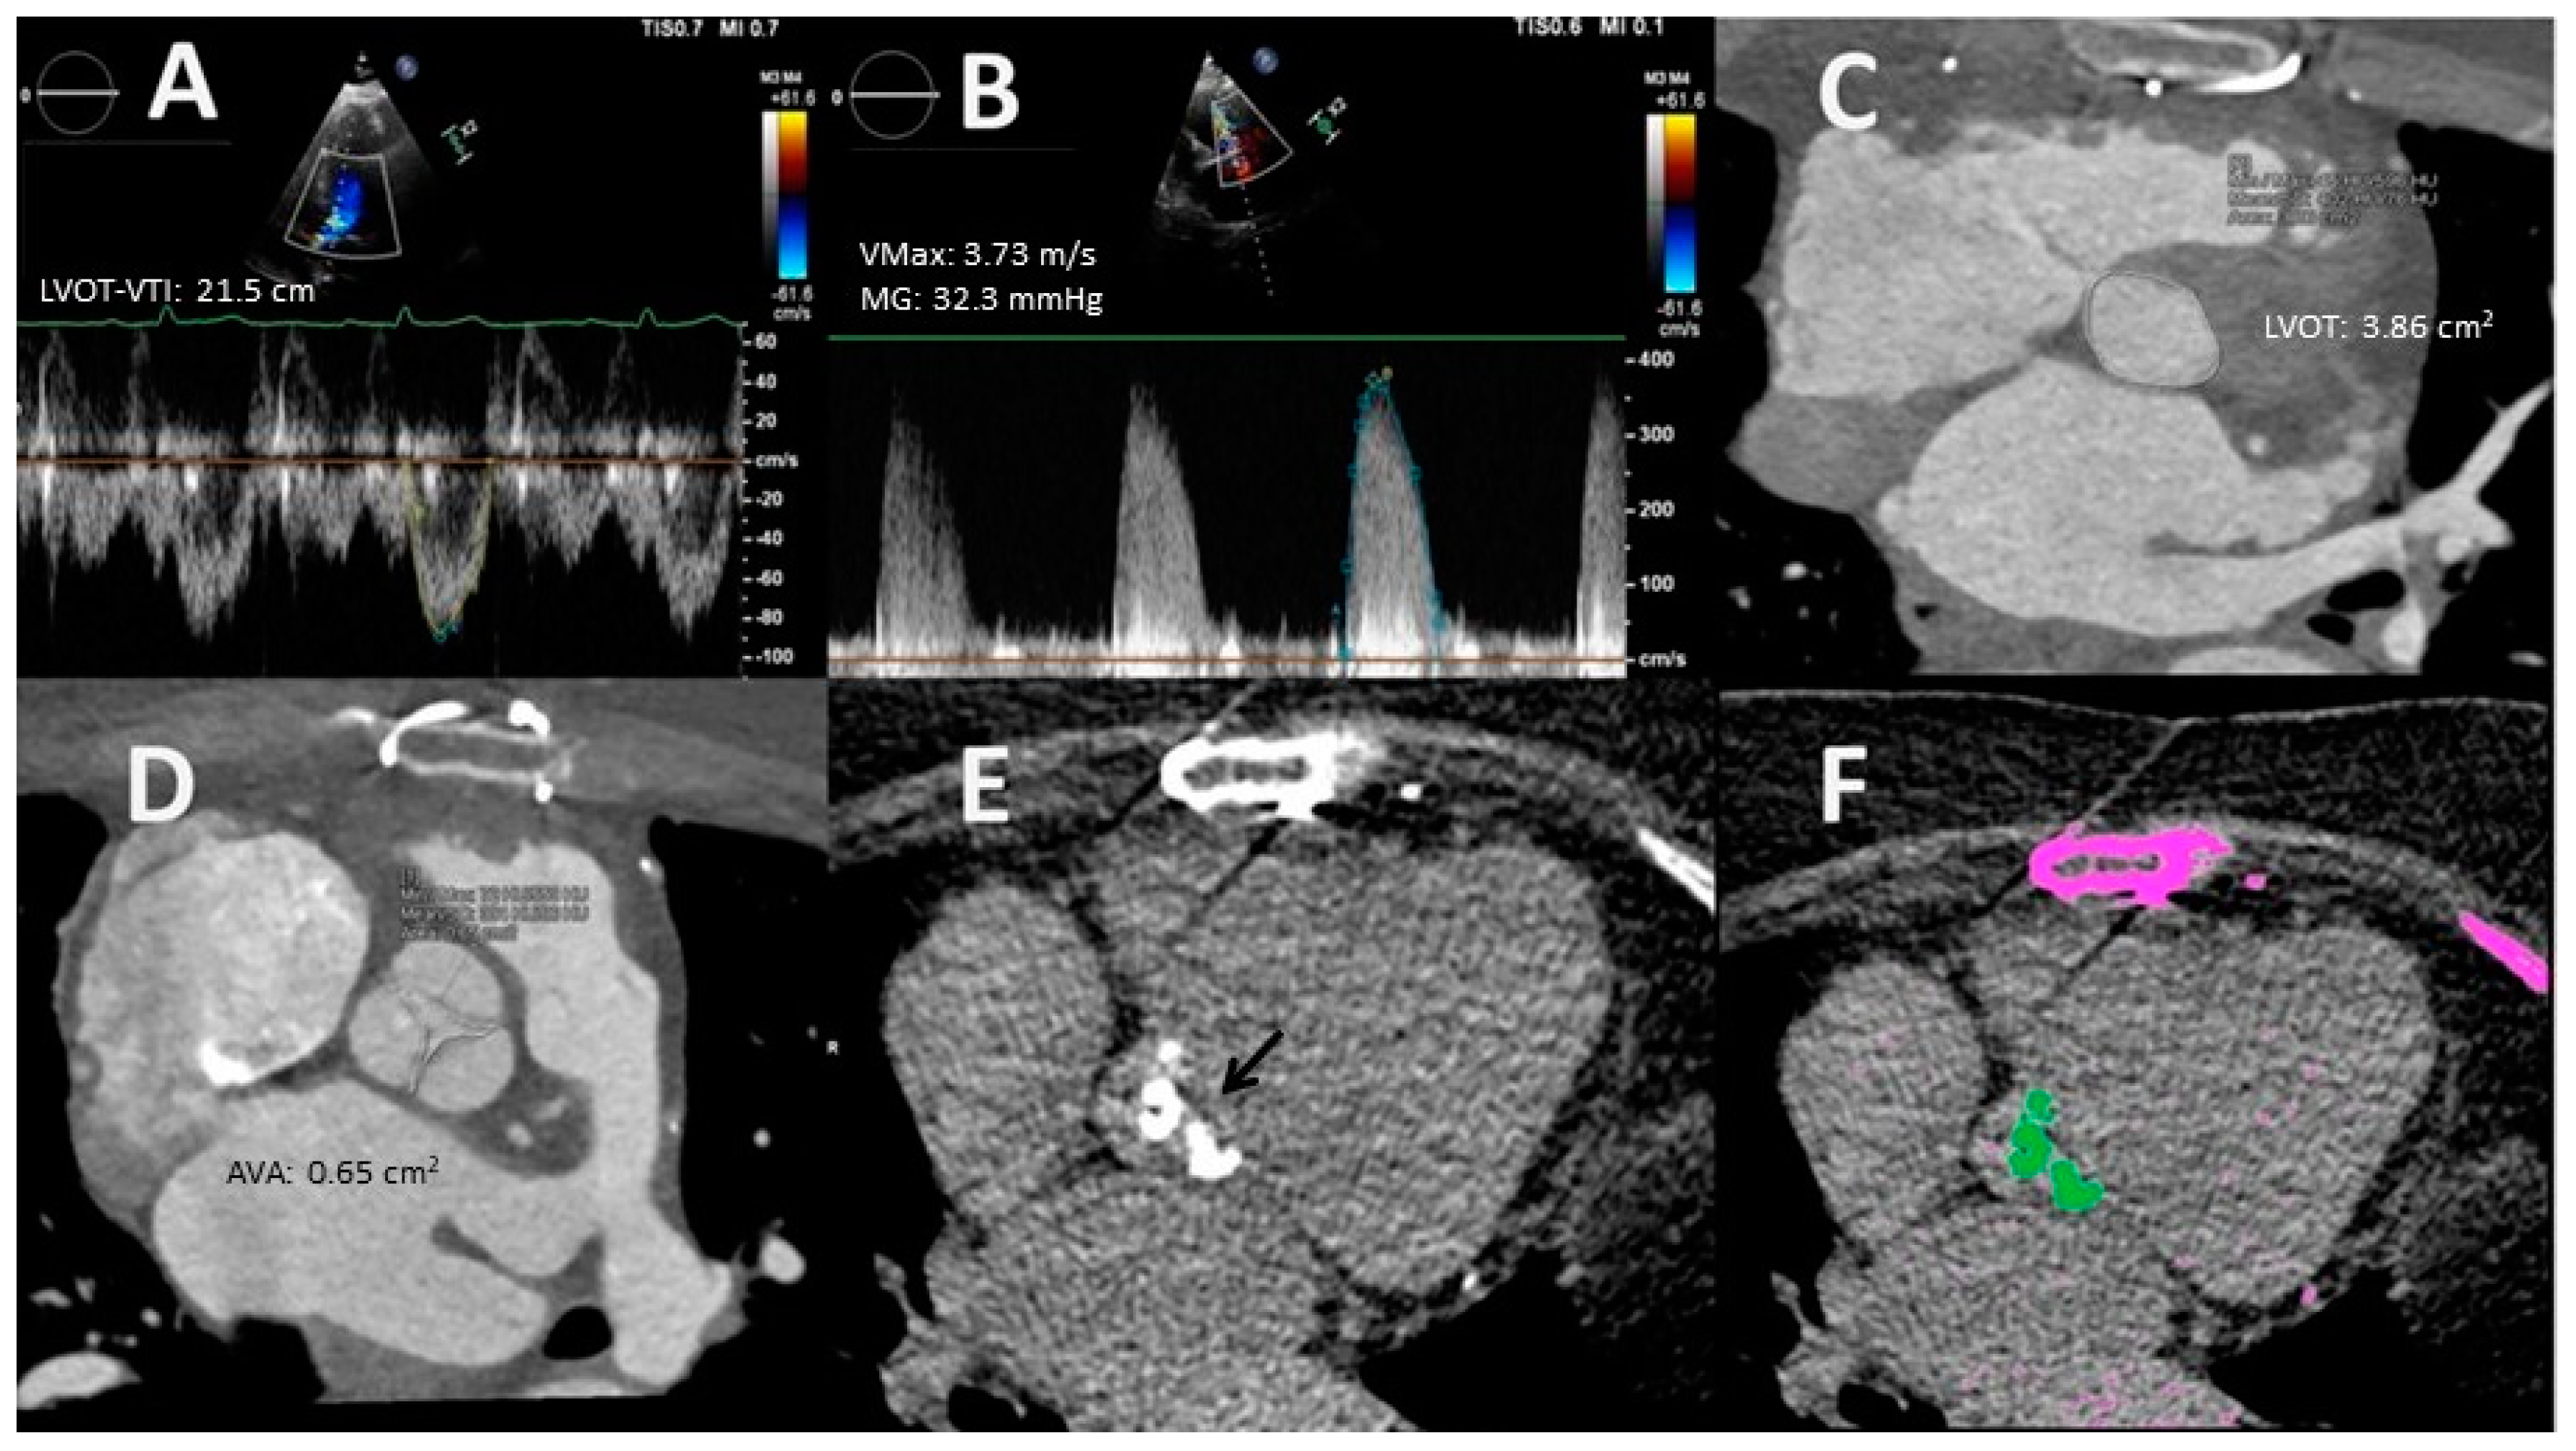

2.3. Multidetector Computed Tomography

- Planimetry. MDCT allows 3D acquisition throughout the entire cardiac cycle using retrospective protocols. Through multislice reconstructions, planimetry of the AV orifice is feasible. Such a measure has shown good agreement with AVA estimated through the CEq [40]. Concerning LVOT size, MDCT assessment is considered to be the gold standard test [23]. Clavel et al. [41] observed that AVA calculated with a hybrid TTE–MDCT method in which the LVOT area used in the Ceq was obtained with MDCT predicted long-term survival with an optimal cut-off value of 1.2 cm2 instead of 1 cm2 [41].